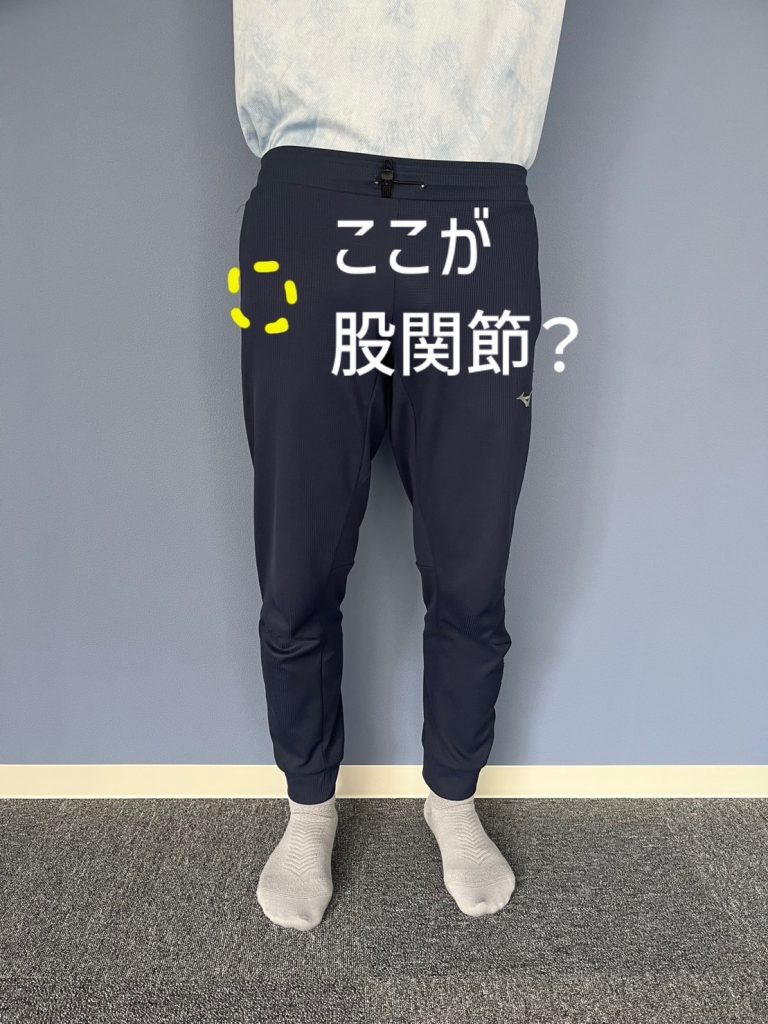

突然ですが、皆さんは“股関節”がどこにあるのかをご存知でしょうか?

もしかすると、股関節を「脚の付け根の外側」だと思っている方が多いかもしれません。

しかし、股関節を模型で確認すると、外側ではなく「中央」に位置していることが分かります。

つまり、股関節の本当の位置は「脚の付け根ラインの中央付近」になります。